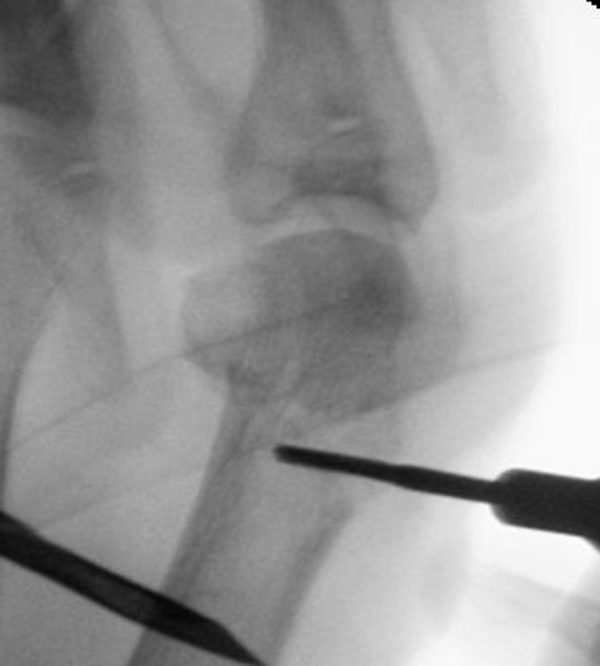

• Positionierung des Bildwandlers: 90° Winkel zum Os metatarsale I. Benötigt wird die Durchleuchtung des Vorfußes a.p., seitlich und schräg.

Zum Lesen der Bildbeschreibung und zur Vollansicht bitte die Bilder anklicken.